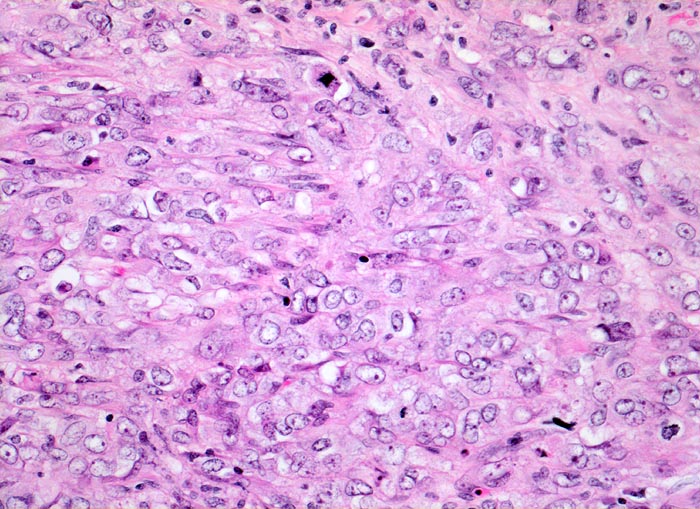

PathoPic – image database / PathoPic ID 4880 - wenig differenziertes Urothelkarzinom

wenig differenziertes Urothelkarzinom

Polymorphe Tumorzellen mit unscharfen Zellgrenzen und bläschenförmigen (=vesikulären) Kernen. Die Tumorzellen lassen kaum eine urotheliale Differenzierung erkennen. Mitosen sind zahlreich.

Chronische Niereninsuffizienz bei bekanntem jahrelangem Analgetikaabusus. Inoperables Urothelkarzinom der Harnblase. Weitere Urothelkarzinome in beiden Ureteren. Die Patientin stirbt am metastasierenden Tumorleiden. (Der Fall liegt mehrere Jahre zurück).